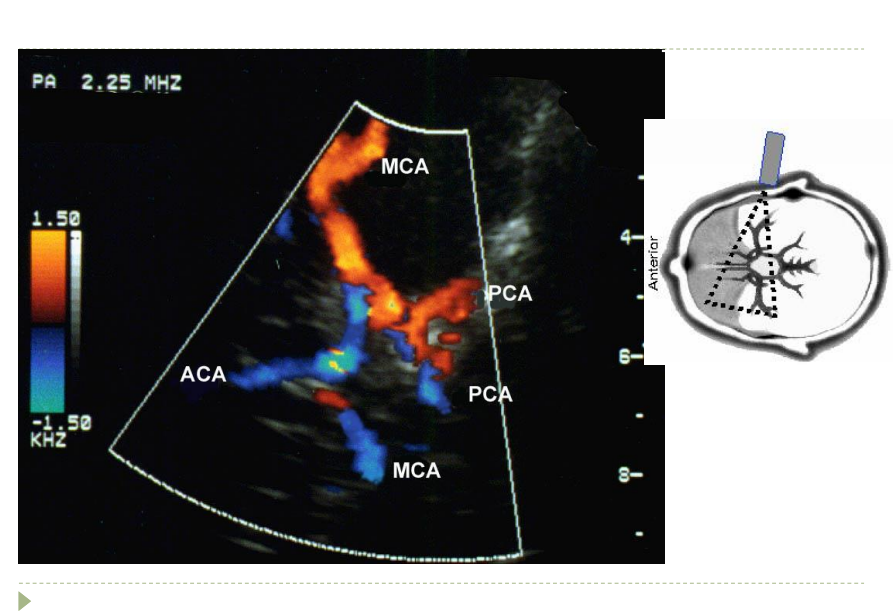

what is this an image of

“Butterfly

MCA-ACA bifurcation